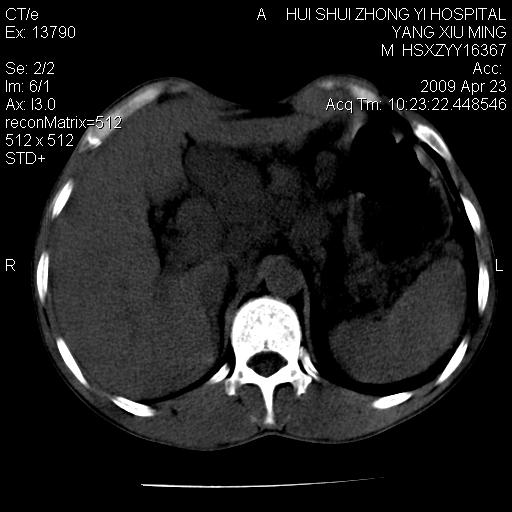

上腹部疼痛一月,呕吐10天,发现左侧颈部包快10天 胸部cr片未见明显异常。

腹膜后淋巴结增大,转移、淋巴瘤?胰腺增大,胰腺炎?占位?颈部考虑增大淋巴结。建议腹部增强扫描。

图像黑了点!

连最基本的ct值都没有测        腹部的窗宽窗位太大了     影响诊断

黑!广泛淋巴结肿大不符合胰腺癌转移。胰腺周围淋巴结肿大致使胰腺看起来大。考虑淋巴瘤可能大。